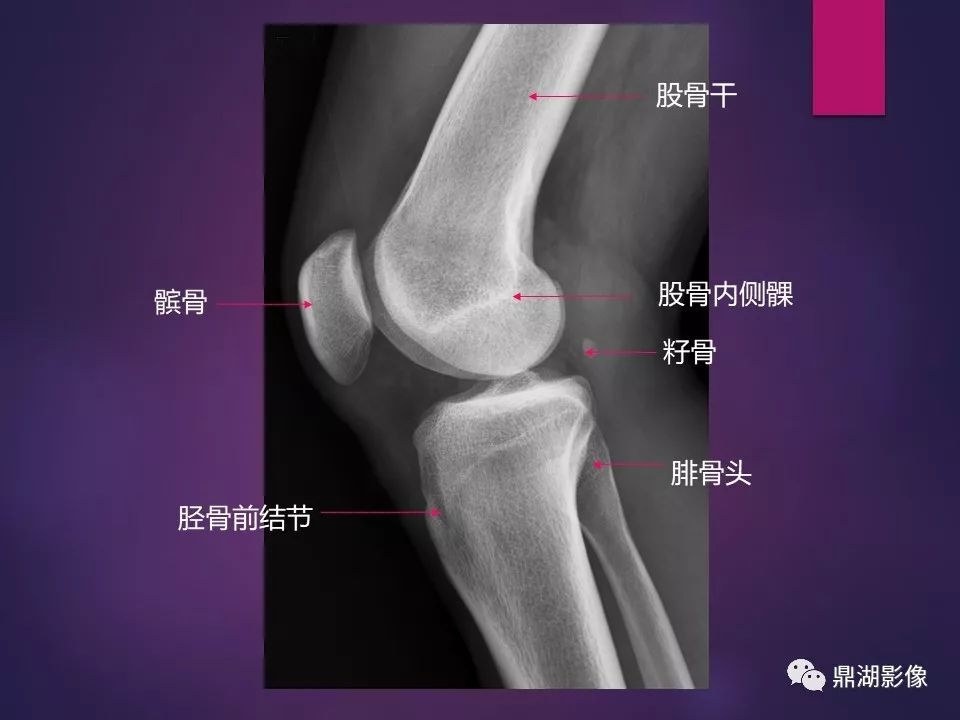

来源于:鼎湖影像 贵阳医学院医学影像系